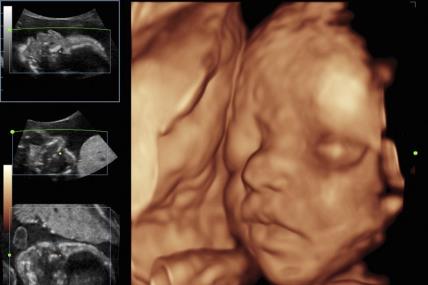

4D ULTRAZVUK: Pogledajte kako izgleda pregled i kako možete videti bebu (VIDEO)

JEDE, KIJA I PLAČE: Pogledajte 4D ultrazvučni snimak koji pokazuje šta beba zaista radi u stomaku (VIDEO)